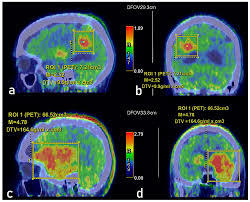

An F-DOPA PET scan is a specialized imaging test used to evaluate dopamine activity in the brain. It is most commonly recommended to diagnose conditions like Parkinson’s disease, movement disorders, certain brain tumors, and other neurological concerns. Because F-DOPA imaging provides highly detailed insights into brain function, it’s essential to get this test done at the Best F-DOPA PET Scan Center Near Me where accuracy and expertise are guaranteed.

A quality diagnostic center ensures that the tracer is handled properly, the imaging is performed correctly, and the interpretation of results is done by a skilled nuclear medicine specialist.